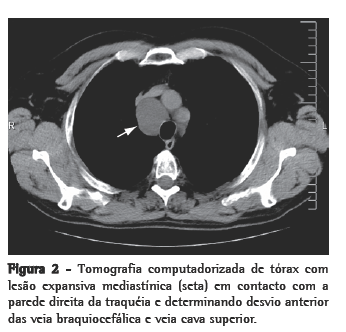

O doente apresentava-se assintomático e sem alterações de relevo ao exame físico-auscultação pulmonar e saturação periférica de oxigênio normais e sem turgescência venosa jugular a 45°. Não apresentava alterações no estudo da função pulmonar, e o exame eletrocardiográfico era normal. Foi efetuada tomografia computadorizada torácica, que revelou uma lesão tumoral mediastínica, em localização paratraqueal direita, com 4,5 cm de diâmetro, em contato com a parede direita da traquéia e determinando desvio anterior das veias braquiocefálica e cava superior. A massa apresentava contornos regulares, baixa densidade espontânea, homogênea e sem realce após administração de contraste (Figura 2).